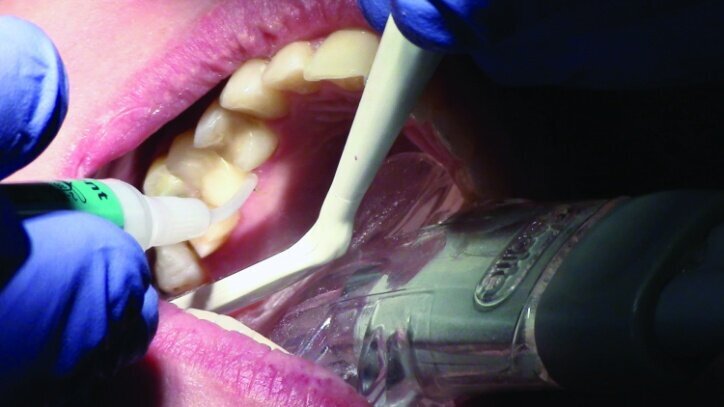

The teeth were isolated using Isolite (Fig. 27). Multilink Primer A/B was scrubbed onto the entire bonding surfaces using a microbrush for 30 seconds. Excess material was dispersed with blown air until the mobile liquid film was no longer visible, leaving a glossy appearing surface (Figs. 28 & 29).

An OptraStick Application Aid (Ivoclar Vivadent) was used to seat the restorations on the teeth because onlays and partial crowns can be difficult to handle. Initial tack curing was completed using a Bluephase curing light (Ivoclar Vivadent) for three seconds at each interproximal area. The resin was then removed easily using a 36/37 scaler from Brasseler. Liquid Strip (Ivoclar Vivadent), a glycerine gel that prevents an oxygen-inhibited layer of the resin cement, was applied to the margins prior to final curing (Figs. 30 & 31).